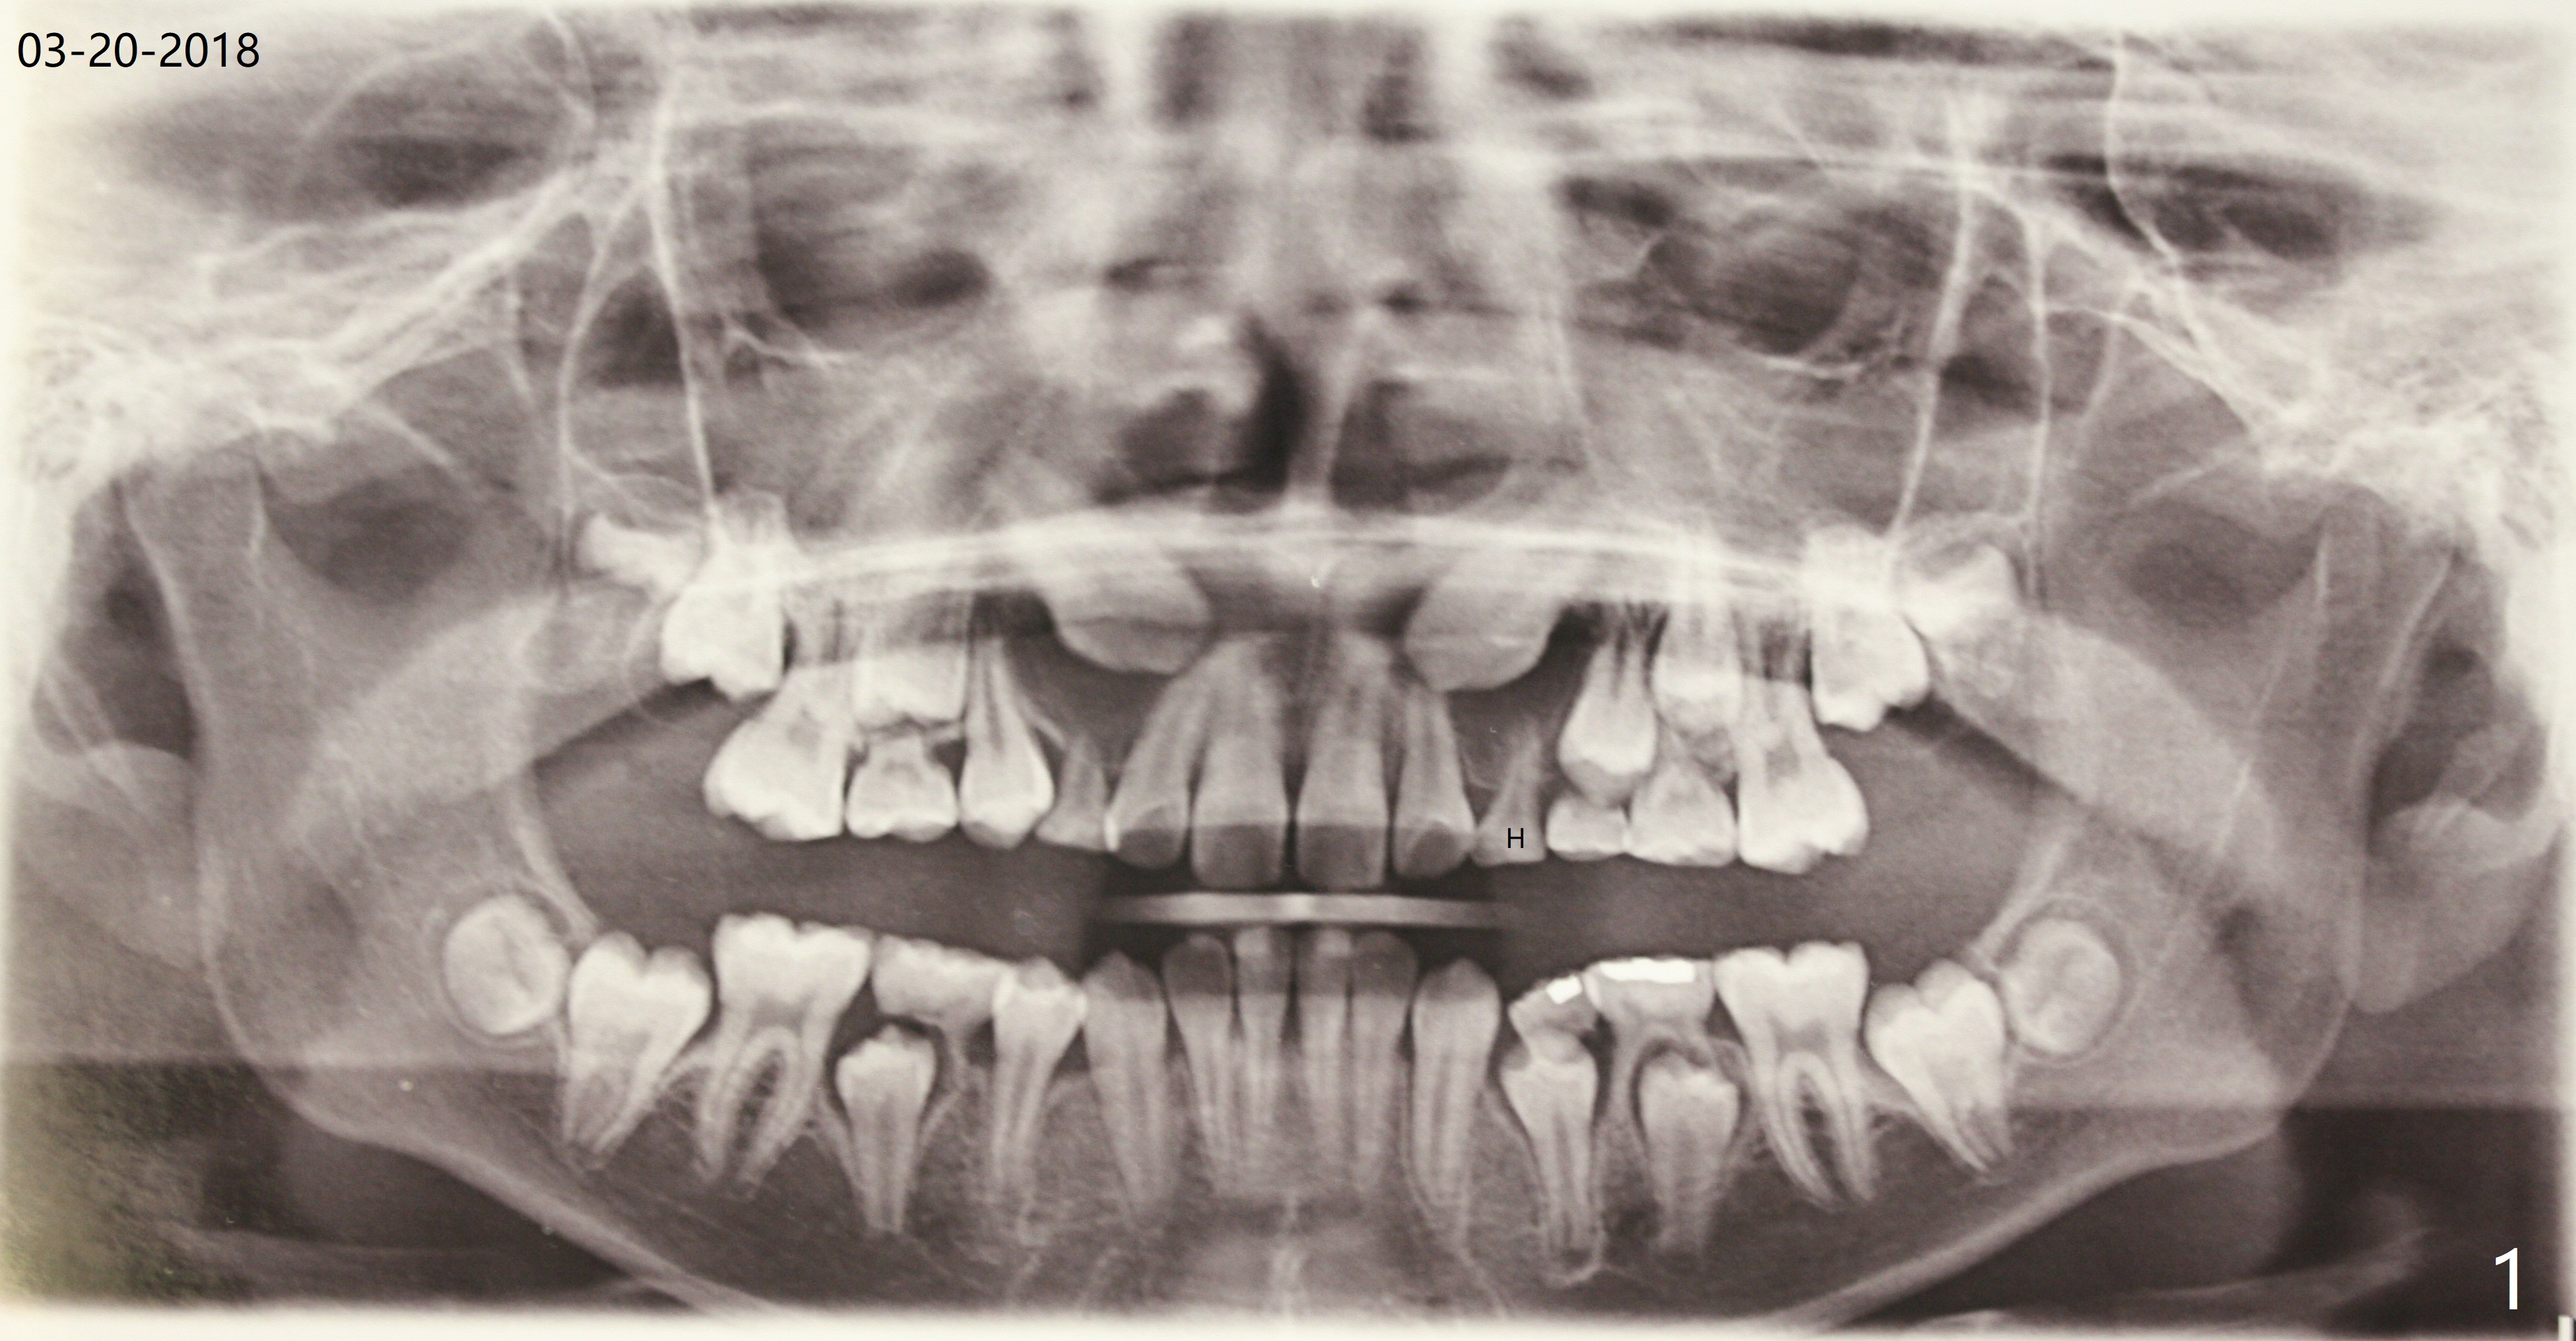

A 13-year-old boy with Class III malocclusion returns with mother from an orthodontic office for extraction of the tooth H with panoramic X-ray taken last year (Fig.1). An interesting finding was present, but not diagnosed a year earlier (Fig.2).

A cystic lesion around each of the impacted permanent upper canines. A normal dental sac or dentigerous cyst?